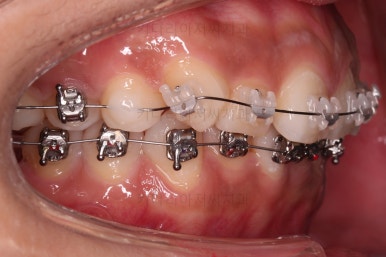

적절한 시점에 발치를 합니다.

발치는 가장 약한 치아 위주로 하게 되고요.

윗니는 이 뽑은 자리를 줄여나가고요.

아랫니는 어금니와 사랑니를 앞으로 당겨옵니다.

물론 다른 치아에 변화를 주지 않기 위해서 미니스크류를 이용합니다.

큰 틀에서는 잘 진행 중인 것 같지만 이번 경우처럼 윗니만 발치, 그리고 발치 위치가 다른 경우, 더군다나 아랫니도 어금니가 없고 사랑니를 당겨오는 경우.

미세한 치아 크기 차이로 마지막 마무리가 오래 걸리는 경우가 많습니다.

100% 중앙선이 잘 안맞는 경우가 많고 미세한 틈새가 오랫동안 잘 안닫히기도 합니다.

이번 환자분도 마찬가지로 중앙선이 100% 안맞았고, 틈새를 타이트하게 닫기 위해 시간이 좀 소요되었습니다.